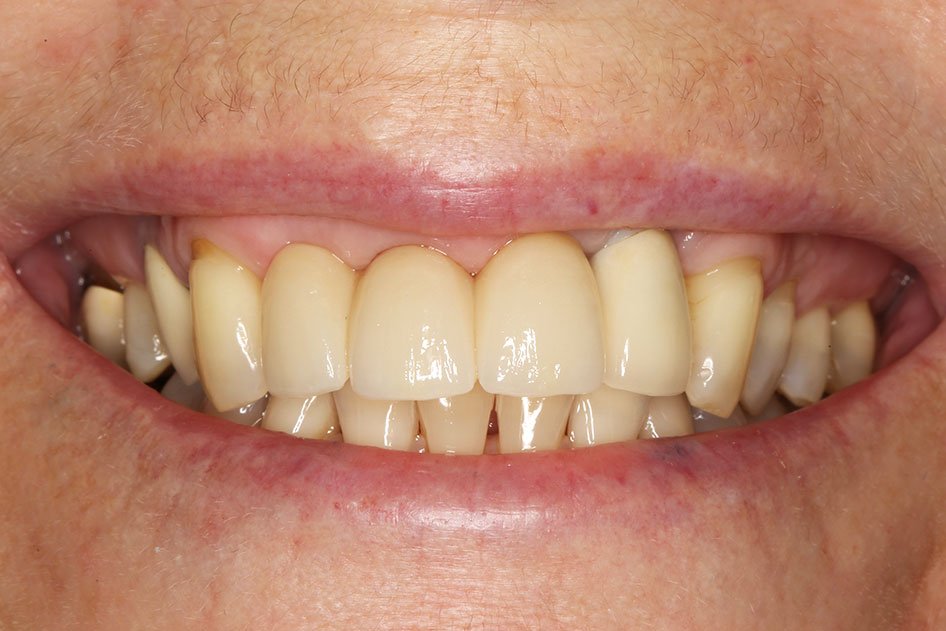

The implant crown is supported by the implant fixture. It is carefully crafted to look and feel like a healthy, natural tooth.

This provides the same stability as natural teeth, making it possible for your replacement teeth to look, feel and function like natural teeth.

Dental implants have a number of advantages over more conventional methods of replacing missing teeth. An implant-supported crown is very similar to your natural tooth because it is fixed permanently, and does not need your other teeth or soft tissues for support.